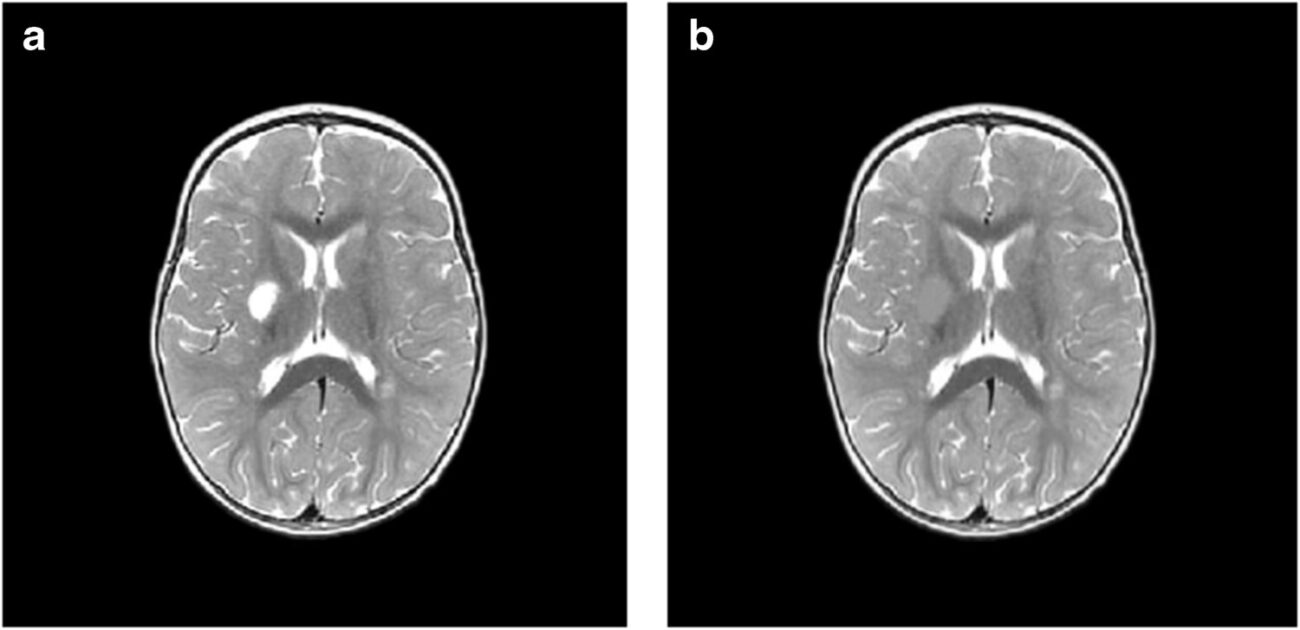

Исследователи проанализировали данные МРТ 35 детей, которые перенесли ишемический инсульт в возрасте до двух лет и лечились в больницах Екатеринбурга, Перми, Челябинска и Тюмени в период с 2015 по 2019 год. Возраст детей на момент инсульта варьировался от четырех дней до одного года 11 месяцев.

Для оценки последствий инсульта исследователи применили современный метод анализа снимков — воксель-базированную морфометрию. Упрощенно эту технологию можно представить так: на каждом МРТ-снимке слой за слоем вручную обводят контуры повреждений области мозга, а специальная компьютерная программа затем вычисляет точный объем этой зоны в кубических миллиметрах.

Такая технология позволяет получить наиболее объективные данные по сравнению с традиционным МРТ-отчетом, направленным на определение качественных характеристик (точных границ инсульта, его локализации). Воксель-базированная морфометрия позволяет получить количественные данные: абсолютный и относительный объем поражения от общего объема мозга. Результат применения такого метода — точные числовые значения для последующего статистического анализа и сравнения.

Оказалось, что инсульты у младенцев и детей, достигших месячного возраста, различаются и по масштабам, и по характеру повреждений. Так, у малышей с перинатальным инсультом объем повреждения мозга оказался намного серьезнее, чем у старших: 7,9% против 1,6% от объема мозга. Также у новорожденных чаще встречались нарушения, затрагивающие кору мозга, смешанные и двусторонние инсульты, а у группы детей от 28 дней до двух лет преобладали локальные подкорковые очаги и повреждения только левого полушария.